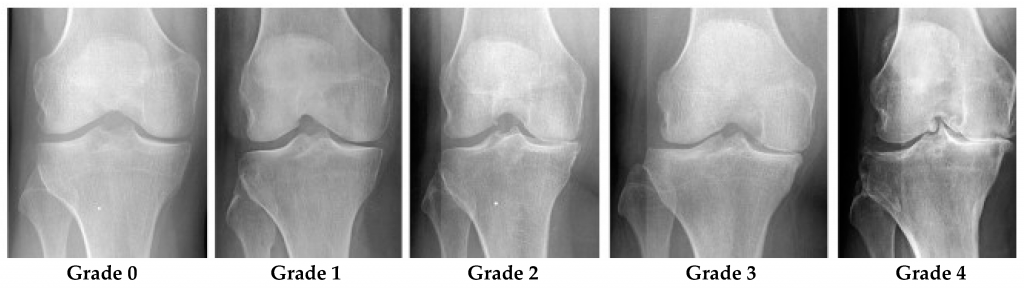

膝关节骨关节炎的X光分级阶段:

分类

Kellgren和Lawrence分类系统在研究中已经有多种变体。以下是原始描述:

- 0级(无)

明显没有骨关节炎X射线变化 - 1级(可疑)

关节间隙变窄和可能的骨赘形成存在疑虑 - 2级(轻微)

Definite osteophytes and possible joint space narrowing - Grade 3 (moderate)

中度的多发性骨赘形成,明显的关节间隙变窄,一些硬化和可能的骨端畸形 - 4级(严重)

大的骨赘形成,明显的关节间隙狭窄,严重的硬化和明显的骨端畸形

尽管病情轻微,但在2级时已被认为存在骨关节炎。